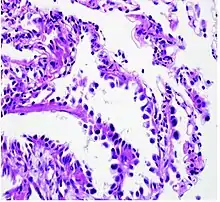

Histopathology of lepidic predominant adenocarcinoma.

• lepidic predominant [18]

Cell patterns identifying subtypes are associated with prognosis, ranging from favorable (lepidic) to intermediate (acinar and papillary) to poor (micropapillary and solid).[2]

As discussed previously, the category of adenocarcinoma includes are range of subtypes, and any one tumor tends to be heterogeneous in composition. Several major subtypes are currently recognized by the World Health Organization (WHO)[1] and the International Association for the Study of Lung Cancer (IASLC) / American Thoracic Society (ATS) / European Respiratory Society (ERS):[30][31][32] lepidic predominant adenocarcinoma, acinar predominant adenocarcinoma, papillary predominant adenocarcinoma, micropapillary predominant adenocarcinoma, solid predominant adenocarcinoma, and solid predominant with mucin production. In as many as 80% of these tumors, components of more than one subtype will be recognized. Surgically resected tumors should be classified by comprehensive histological subtyping, describing patterns of involvement in increments of 5%. The predominant histologic subtype is then used to classify the tumor overall.[2] The predominant subtype is prognostic for survival after complete resection.[33]